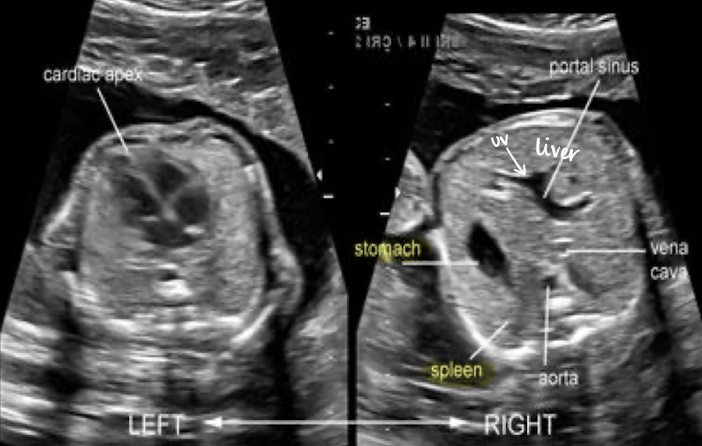

liver

large compared to other abdominal organs

occupies upper right abdomen

left lobe is larger in utero

SONO:

homogeneous, moderate echogenicity

helpful for determining situs and obtaining AC measurement

spleen

in LUQ

increases in size during gestation (biggest in 3rd trimester)

best images in TRV plane; to left of stomach

homogeneous

similar echogenicity to kidney

less echogenic than liver